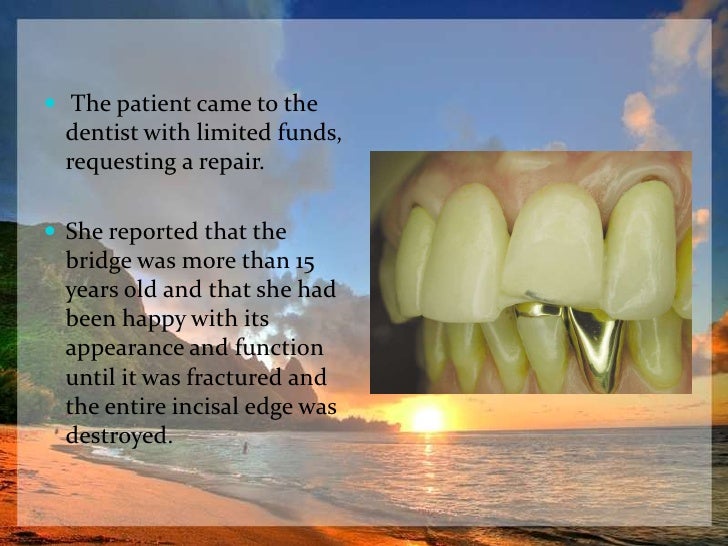

A Technique For Repair Of A Fractured Porcelain-Fused-to-Metal Bridge

www.dentistrytoday.com

www.dentistrytoday.com

Repairing Fractured Pfm | PPT

www.slideshare.net

www.slideshare.net

Repairing Fractured Pfm

www.slideshare.net

www.slideshare.net

Repairing Fractured Pfm

www.slideshare.net

www.slideshare.net

Repairing Fractured Pfm

www.slideshare.net

www.slideshare.net

Repairing Fractured Pfm

www.slideshare.net

www.slideshare.net

Repairing Fractured Pfm

www.slideshare.net

www.slideshare.net

A Technique For Repair Of A Fractured Porcelain-Fused-to-Metal Bridge

www.dentistrytoday.com

www.dentistrytoday.com